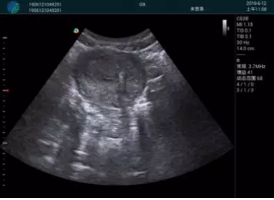

清晰顯示孕囊,通過軟件包計(jì)算孕齡7w+6d

M20實(shí)時(shí)引導(dǎo),術(shù)中清晰顯示孕囊被破壞和抽吸針的過程,清晰顯示吸引針

抽吸結(jié)束后縱切子宮,孕囊已被完全抽吸,未見明顯殘留

橫切子宮,發(fā)現(xiàn)右側(cè)宮腔靠近宮角處有少許脫模樣殘留

M20引導(dǎo)下,抽吸針找到右側(cè)宮角處再次清掃

二次抽吸后再次進(jìn)行超聲檢查,宮腔未見殘留,宮腔線清晰顯示